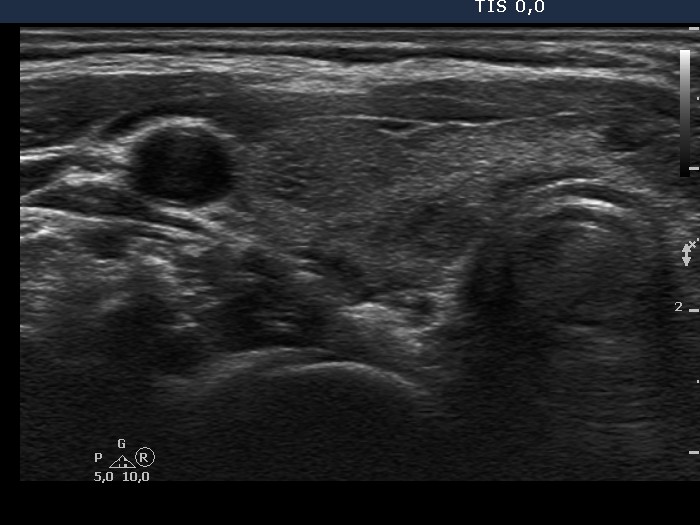

First examination (first and second rows):

Ultrasonography: the thyroid was echonormal and contained numerous hypoechogenic areas. The echogenicity index was around 25%. The vascularization was moderately increased. Neither of the hypoechogenic areas corresponded to a nodule.Cytology: was performed from the largest hypoechogenic area in the left thyroid.

Cytological diagnosis: benign, atypia of a hormonal reason.

Ultrasonography: the echogenicity index decreased to 15%. The vascularization also decreased. The lesion aspirated on the first visit significantly decreased in size.